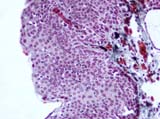

Tumor Histology